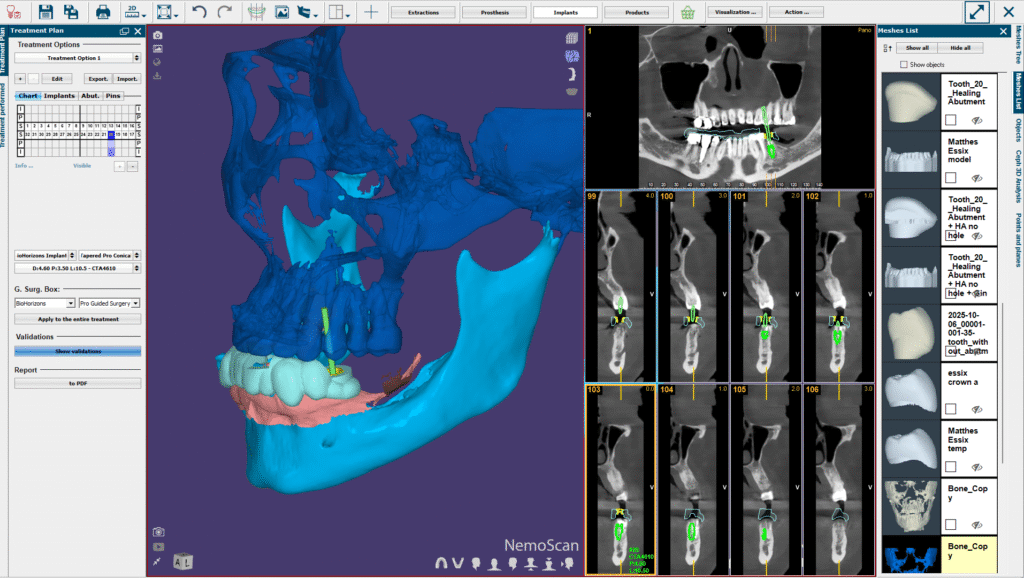

We use NemoScan Implant Planning Software from Nemotec- SPAIN, a Henry Schein Company. NemoScan is the worlds most advanced implant planning software that gives us abilities that no other software on the market gives.